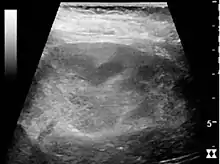

Acute pyelonephritis with increased cortical echogenicity and blurred delineation of the upper pole.[20]

Ultrasound findings that indicate pyelonephritis are enlargement of the kidney, edema in the renal sinus or parenchyma, bleeding, loss of corticomedullary differentiation, abscess formation, or an areas of poor blood flow on doppler ultrasound.[21] However, ultrasound findings are seen in only 20% to 24% of people with pyelonephritis.[21]